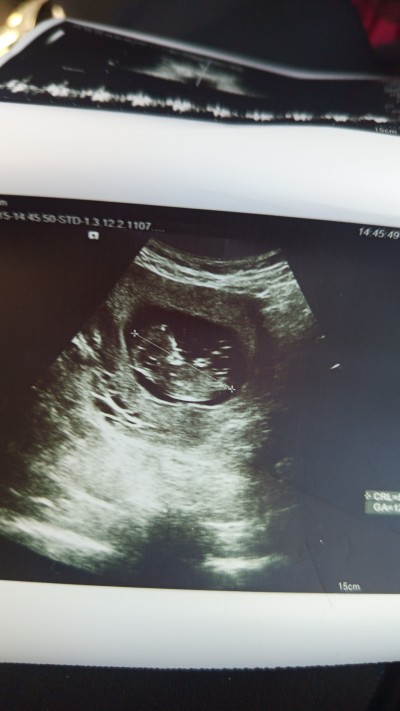

Arkadaşlar 18 haftalık olucaz daha öğrenemedim bir tahminde bulunurmusunuz

imageburda daha 13 haftalık falan

Gebelik haftası 18

Eğer yanılmıyorsam nub çizgisi kız gibi duruyor chatcpt ye sor istersen at resmi yorumlasin